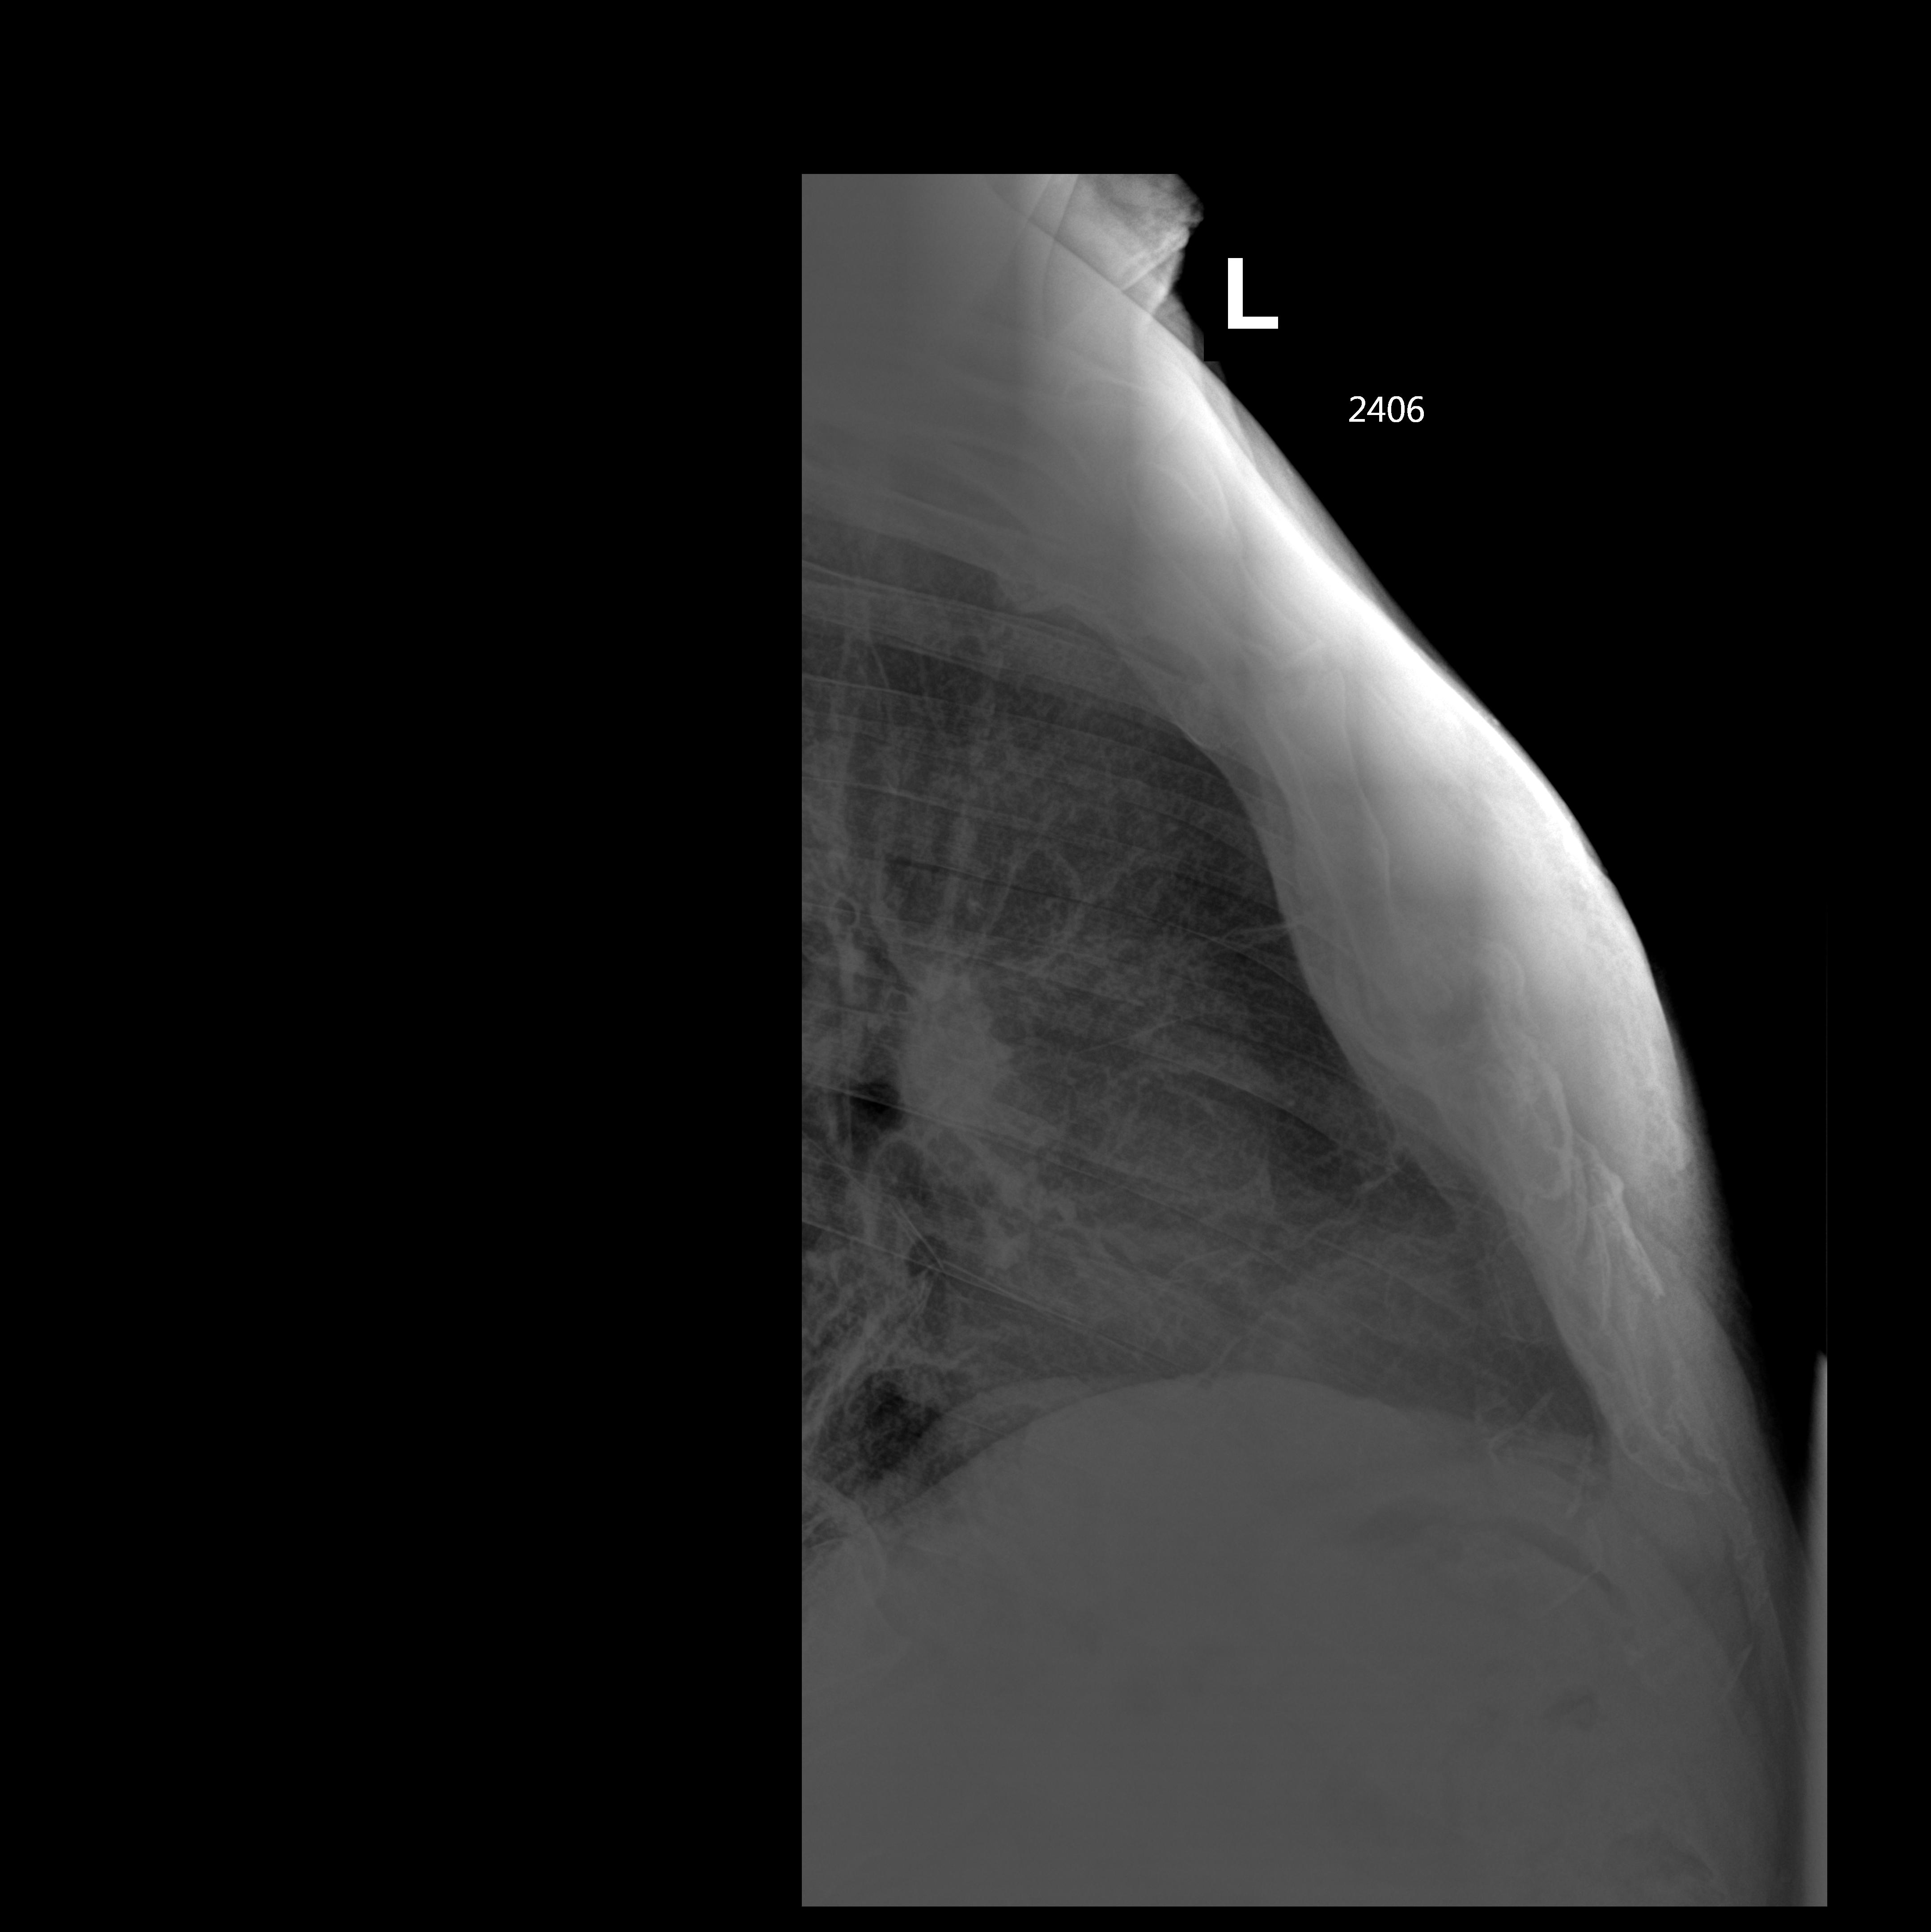

Перелом грудины, гнойное воспаление мягких тканей

Мужчина, перелом грудины.

zvinys_0.jpg